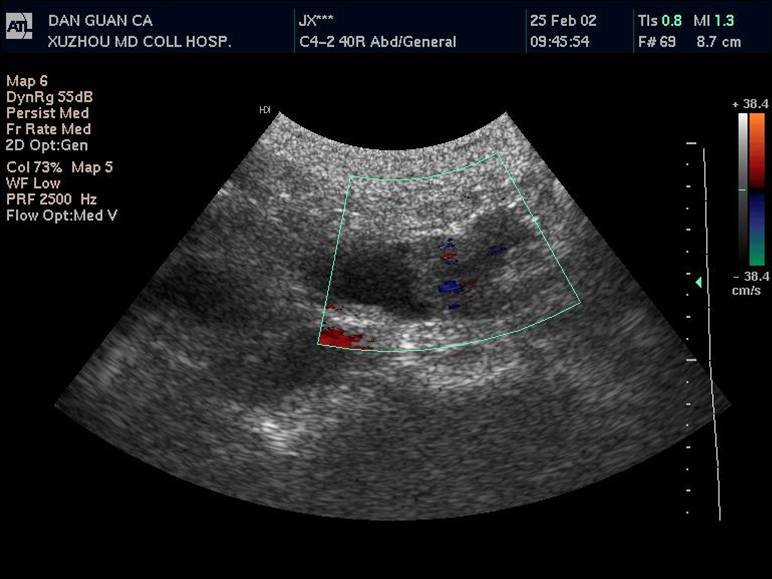

1 胆管结石